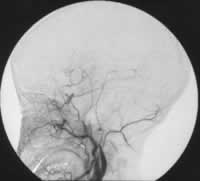

近日,重庆第三军医大学西南医院神经外科采用颅内外动脉搭桥术结合血管内介入栓塞术成功治愈1例颈内动脉海绵窦段巨型梭形动脉瘤。该患者年仅10岁,经检查发现其动脉瘤直径超过4 cm,且合并基底动脉闭塞,颅内血供仅靠双侧颈内动脉维持。经过认真讨论后,专家们利用截取的患者自体桡动脉,成功地将颞浅动脉与大脑中动脉搭桥连接。1周后,脑血管造影显示患者颅内外血管通畅,专家遂实施介入手术,对患侧颈内动脉进行血管内栓塞。患者术后恢复良好,生命体征平稳,已康复出院。, http://www.100md.com